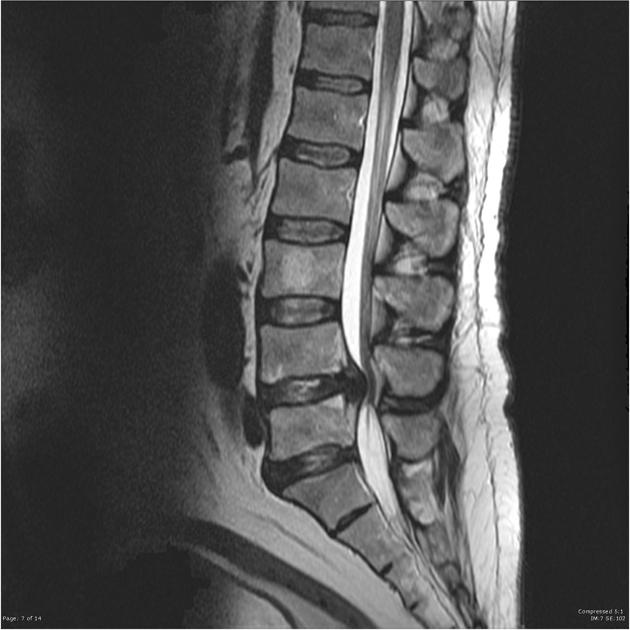

Hình ảnh & cách đánh giá mức độ hẹp

- Mức độ chèn ép trong ống sống thường được đánh giá rõ nhất trên ảnh MRI mặt phẳng axial (mặt cắt ngang).

- Ảnh bên phải minh họa vùng bị hẹp ống sống trên mặt phẳng sagittal (mặt cắt dọc bên) để giúp dễ hình dung tổng thể vị trí.

- Ảnh bên phải là tiêu chuẩn phân loại mức độ hẹp ống sống:

- Normal/Mild (Bình thường/nhẹ)

- Moderate (Trung bình)

- Severe (Nặng)